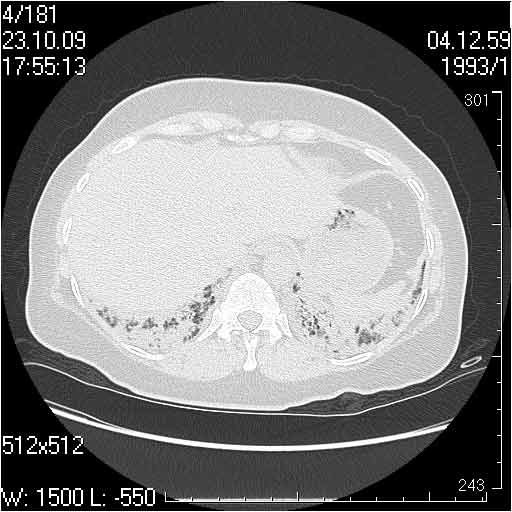

Случай №1

Женщина 50 лет.

Случай 1: изменения характерны для интерстициальной пневмонии (IIP/UIP idiopathic interstitial pneumonia/usual interstitial pneumonia); говорить о конкретной форме без открытой биопсии затруднительно.